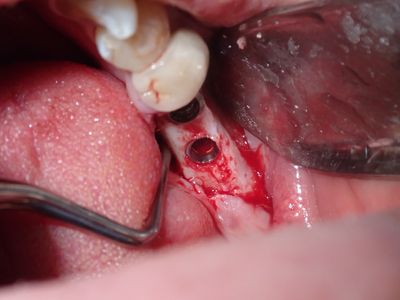

relatively straight forward implant placement, some bone expansion and countersinking. buccal bone thin, grafted with sticky bone from allograft folloewd by collagen mmebrane soaked in prf fluid, additional fibrin membrane used